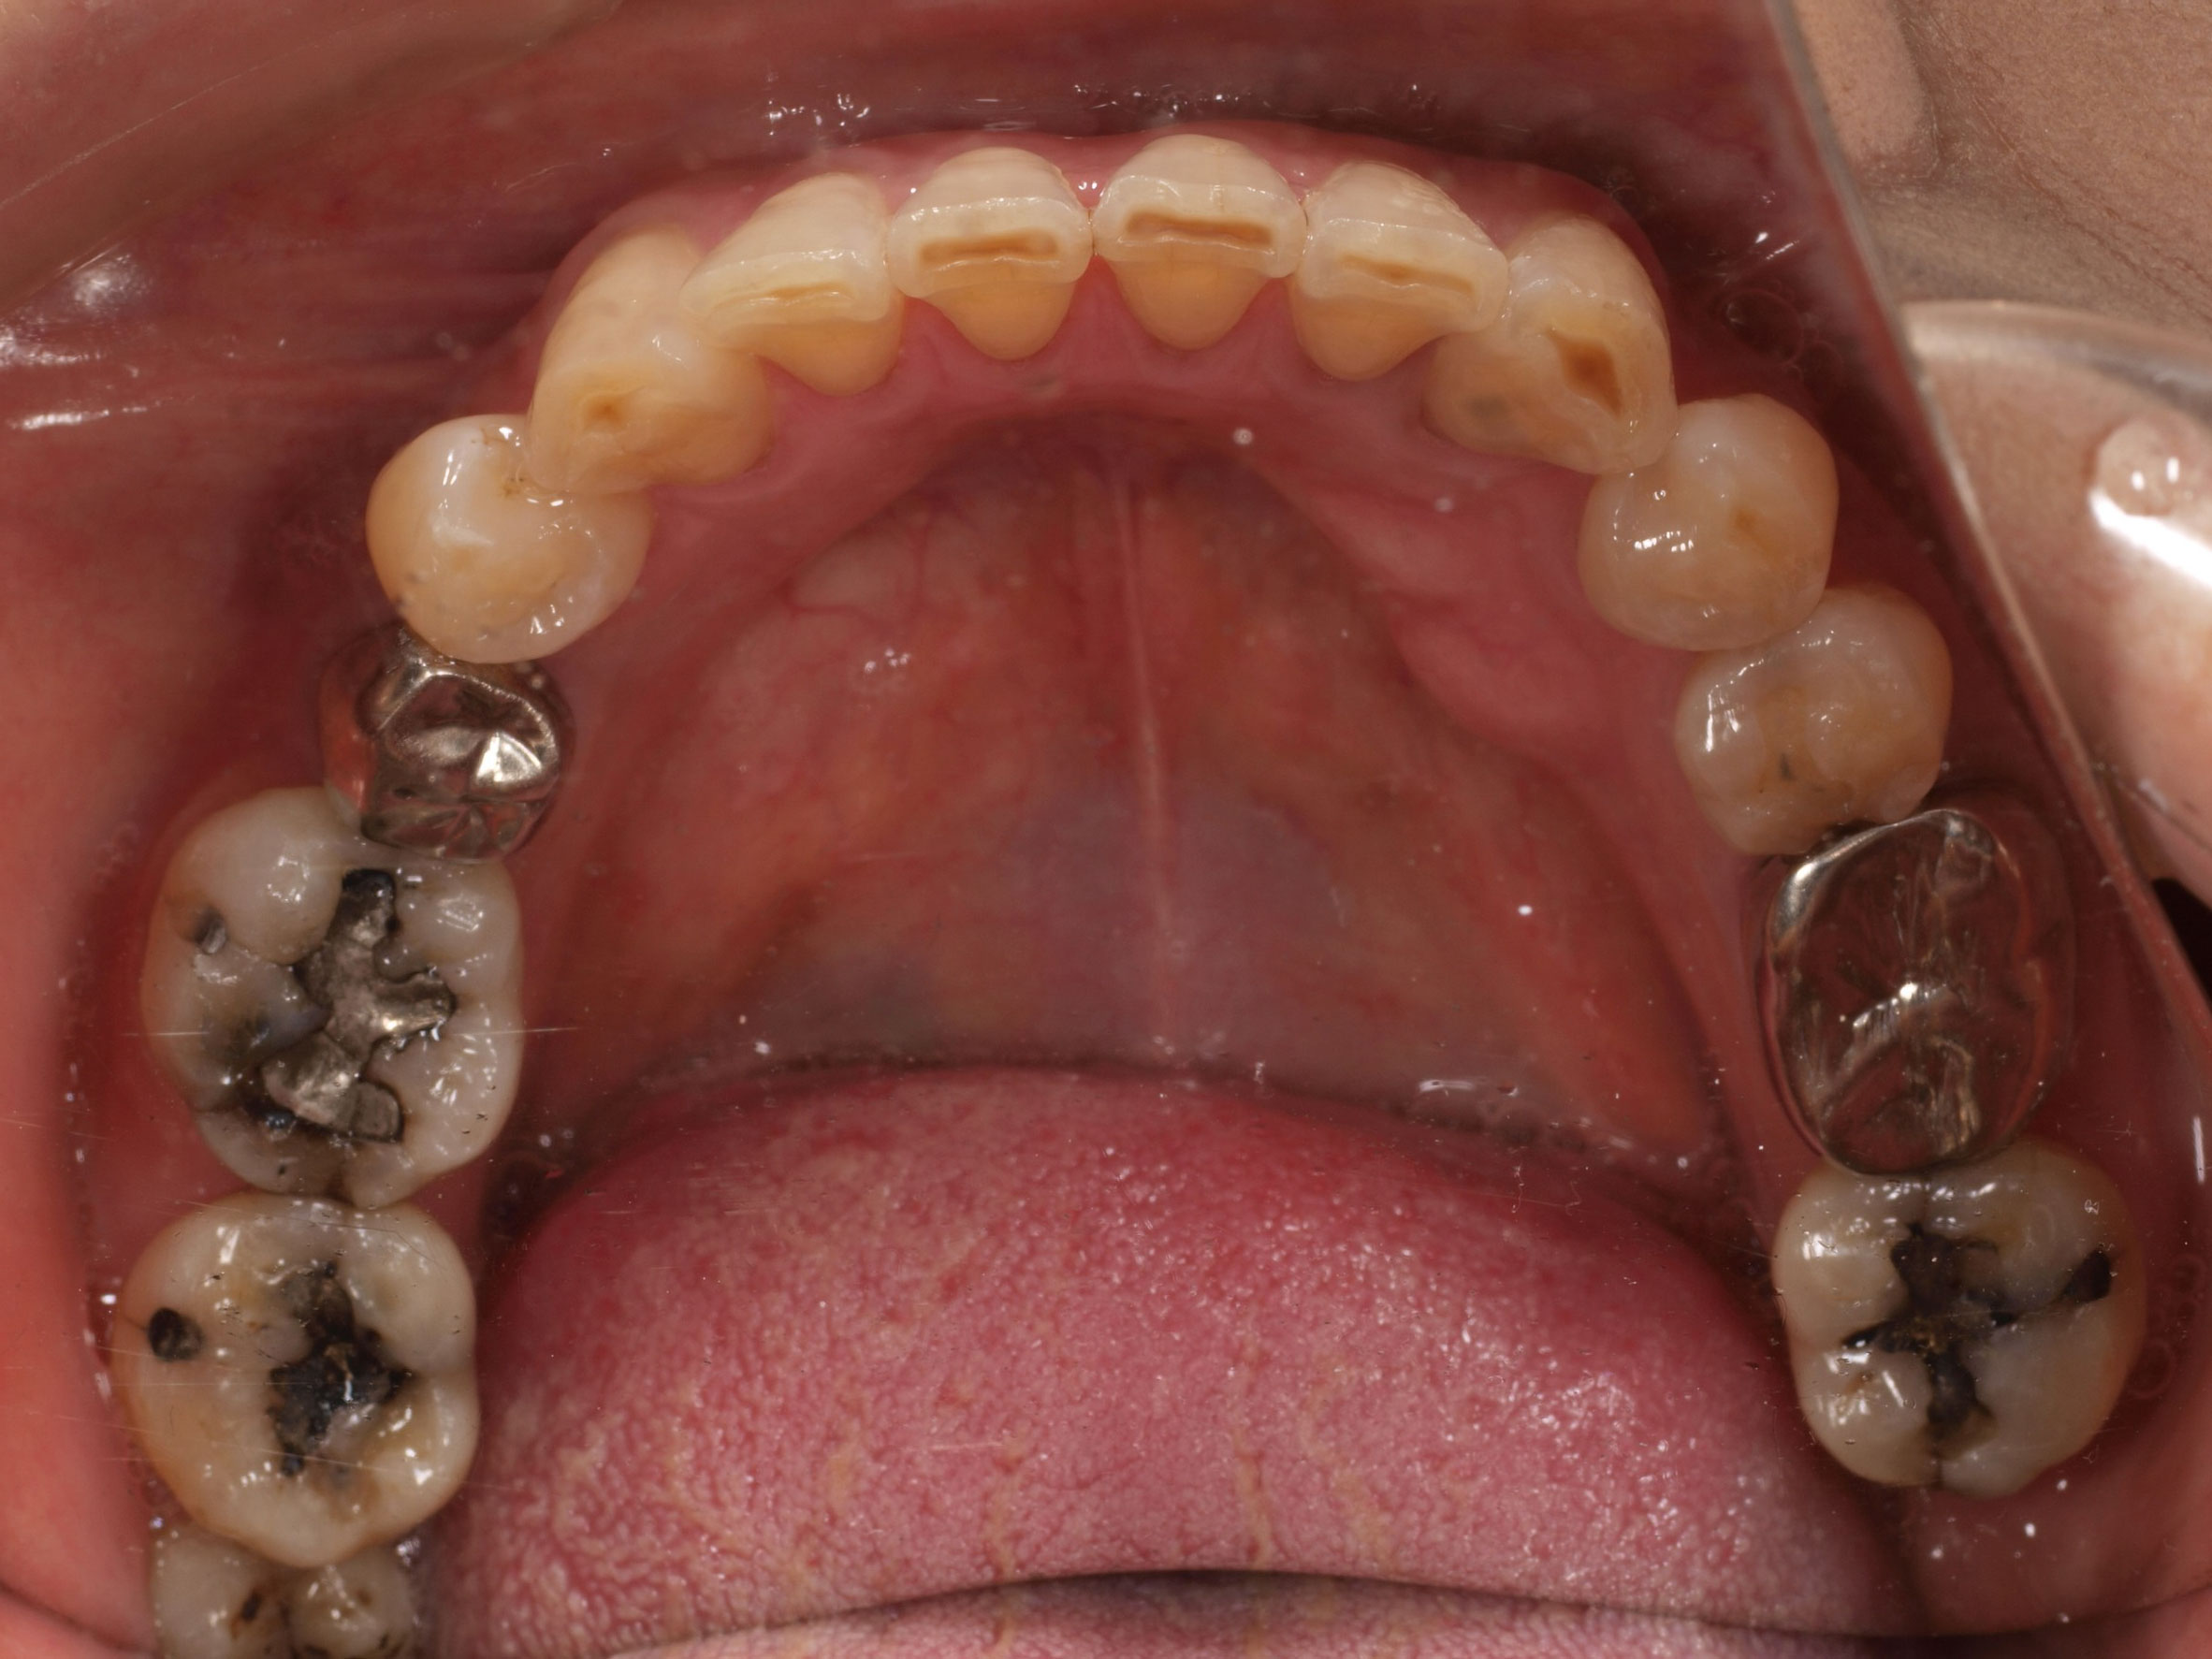

- 主訴

- 入れ歯が気持ち悪く、しっかりと食べれない。本当につらい。美味しく食べて、豊かな人生を過ごしたい。

- 処置内容

- 上顎6本(オールオン6)

- 治療費用

- 上顎350万円(税込)

- 治療期間

- 上顎1年(仮歯まで8か月)/約10回

- リスク

- 上部構造物、仮歯の破折、術後の腫れ(3日)、人工歯根脱落のリスクがあります